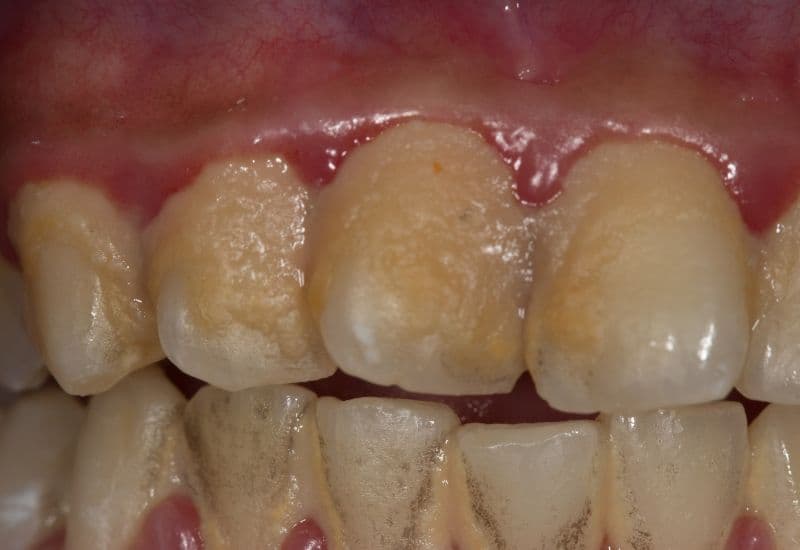

– Tích tụ mảng bám: Sâu răng bắt đầu từ mảng bám. Mảng bám là lớp mỏng trên bề mặt răng, chủ yếu bao gồm vi khuẩn và thức ăn thừa, đặc biệt là thực phẩm nhiều đường và tinh bột. Vi khuẩn trong mảng bám sử dụng các thực phẩm đó để sản xuất acid.

Sâu răng bắt đầu từ mảng bám; mảng bám là lớp mỏng trên bề mặt răng, chủ yếu bao gồm vi khuẩn và thức ăn thừa.

– Phân hủy men răng: Acid do vi khuẩn sản xuất phá hủy men răng, lớp bảo vệ cứng nhất của răng. Khi acid tiếp xúc với men răng, nó lấy đi các khoáng chất từ men răng qua quá trình gọi là khử khoáng. Quá trình này làm yếu men răng, tạo ra các lỗ trên men răng.

– Phân hủy ngà răng: Khi mảng bám tiếp tục tích tụ và acid tiếp tục được sản xuất, các lỗ trên men răng phát triển rộng hơn và sâu hơn, tới lớp ngà răng nằm dưới men răng. Ngà răng mềm hơn men răng và dễ bị tổn thương hơn bởi acid. Sự phân hủy ngà răng diễn ra nhanh hơn nhiều so với men răng.